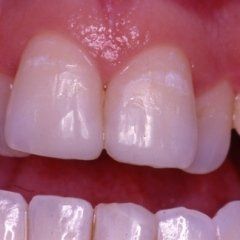

Odontoiatria e conservativa

L’enorme diffusione ancora oggi riscontrabile della carie dentaria, unita a traumi, difetti di mineralizzazione o ipoplasie dello smalto determinano la necessità di dover ricorrere ad un restauro dei tessuti dentari lesionati. Il continuo miglioramento dei materiali e di conseguenza delle tecniche hanno altresì ampliato il raggio di azione della cosiddetta conservativa che con il ricorso al trattamento endodontico in caso di lesioni particolarmente gravi, occupa circa i due terzi dell’attività del dentista. In considerazione di questo fatto quindi, oltre all’evidenza che il trattamento restaurativo diretto è in genere il primo atto odontoiatrico che si effettua su una corona dentale lesionata, emerge la necessità che questa terapia sia ben eseguita ed in armonico rapporto con le strutture parodontali ed endodontiche.